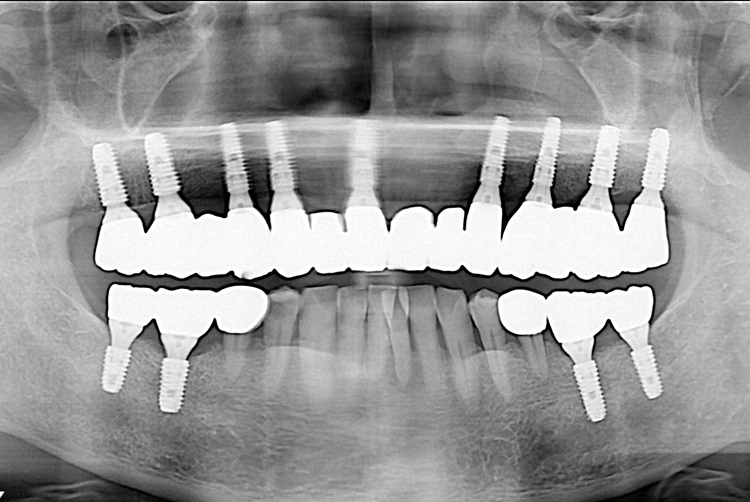

[임플란트] 임플란트

치료전 : 2019-07-18

치료후 : 2019-10-01

세종치과는 많은 환자와 다양한 케이스를 바탕으로 항상 편안한 임플란트 수술을 제공하고자 노력하고,

오래동안 튼튼히 쓸 수 있는 임플란트 수술을 가장 큰 목표로 삼고 있습니다